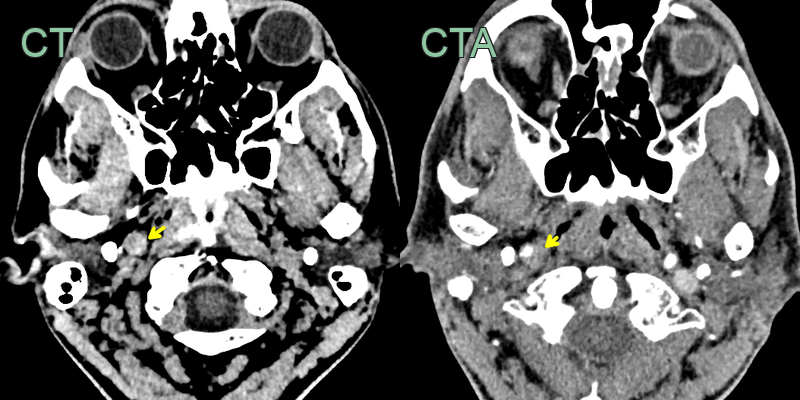

- 50-year-old patient presented with sudden onset right sided neck pain and a Horner's syndrome (blurred vision, right sided miosis and ptosis).

- The initial CT and CTA showed a hyperdense rim around an expanded right ICA below the skull base without a significant stenosis (yellow arrow).